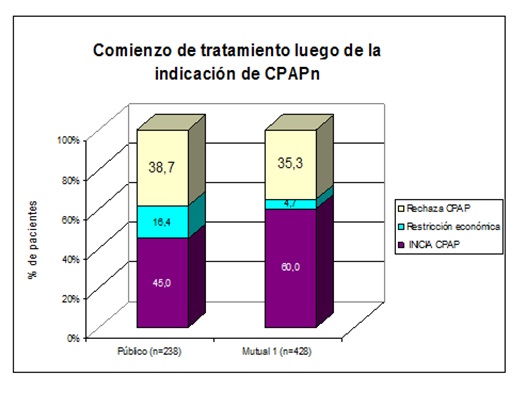

Comenzaron el tratamiento con CPAPn el 45% de los pacientes del Hospital de Clínicas y el 60% de los pacientes del área mutual. La forma de acceso al tratamiento fue: sin costo (empleados con aporte a la seguridad social); con costo parcial (seguros de salud y cajas de auxilio) y con costo completo a cargo del paciente. La imposibilidad de acceder al equipo por restricción económica no constituyó el mayor obstáculo para el comienzo del tratamiento (16,4% y 4,7%). El resto de los pacientes que no comenzó el tratamiento, pertenece a un grupo denominado “rechazo inicial del tratamiento” cuya tasa fue de 38,7% y 35,3%. (Figura 13).

Figura 13: El 45% de los pacientes del HC y el 60% del sistema mutual comenzaron tratamiento con CPAPn. No pudieron hacerlo por imposibilidad económica de adquirir el equipo, el 16,4% y el 4,7%. El 38,7% y el 35,3% rechazaron el tratamiento.